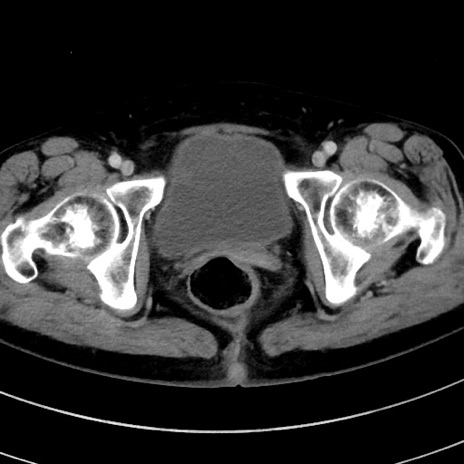

冠状断像